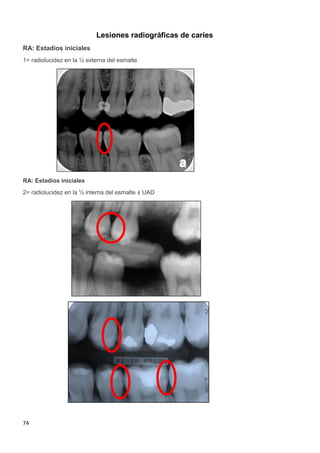

2.2.2.2 Clasificación radiográfica de las lesiones coronales de caries

La información radiográfica contribuye significativamente a los hallazgos clínicos en

términos del hallazgo de lesiones en diferentes estadíos de progresión29-32

. Las

radiografías ayudan a estimar la profundidad de desmineralización por caries en el

esmalte y la dentina. La profundidad no siempre está asociada con la presencia de

Sistema de registro ICDAS Radiográfico

Categorías

de

Caries

ICCMS™

0

Sin radiolucidez

Ausencia de radiolucidez

RA:

Estadíos

iniciales

RA 1

Radiolucidez en 1/2

externa del esmalte

RA 2

Radiolucidez en la 1/2

interna del esmalte ± UAD

(Unión amelo-dentinal)

RA 3

Tabla 3. Sistema ICDAS/ICCMS™ de registro radiográfico.